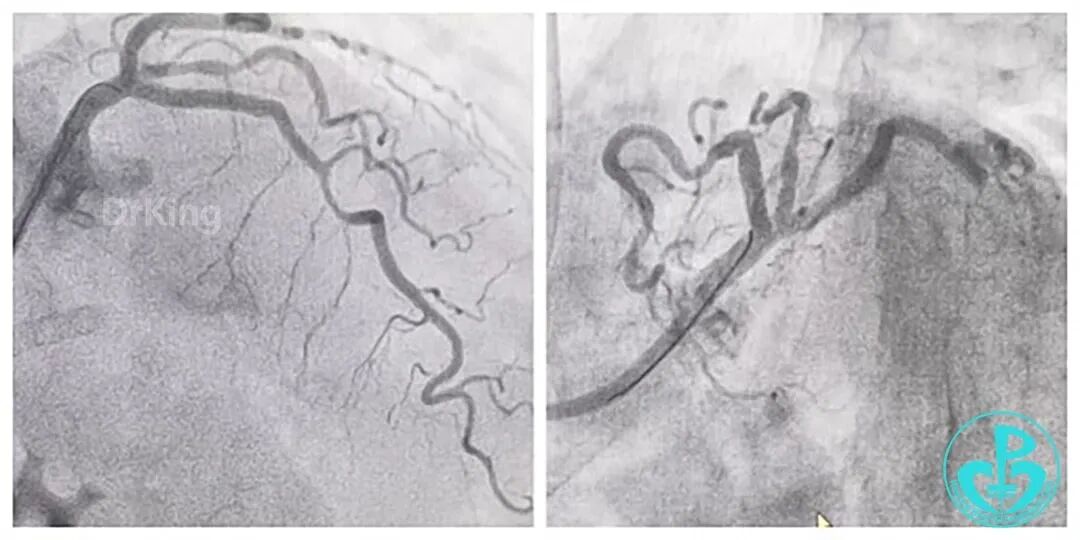

IVUS确认导丝全程位于真腔,夹层已延伸进展至PLA,先于近段支架1枚,压闭破口,RCA中远段真腔未恢复血流,患者出现室速室颤,立即给予电除颤、心脏按压,同时穿刺侧上肢约束,避免导管导丝脱出。

依次由远及近(PLA→dRCA-mRCA)全程DES,NCB优化扩张,RCA血流恢复,间隔支侧支循环恢复,病情趋于稳定。